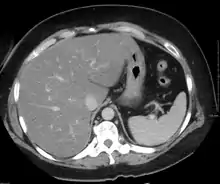

Imaging studies are often obtained during the evaluation process. Ultrasonography reveals a "bright" liver with increased echogenicity. Medical imaging can aid in diagnosis of fatty liver; fatty livers have lower density than spleens on computed tomography (CT), and fat appears bright in T1-weighted magnetic resonance images (MRIs). Magnetic resonance elastography, a variant of magnetic resonance imaging, is investigated as a non-invasive method to diagnose fibrosis progression.[28] Histological diagnosis by liver biopsy is the most accurate measure of fibrosis and liver fat progression as of 2018.[6] Conventional imaging methods, such as ultrasound, CT and MRI, are not specific enough to detect fatty liver disease unless fat occupies at least 30% of the liver volume.[29]